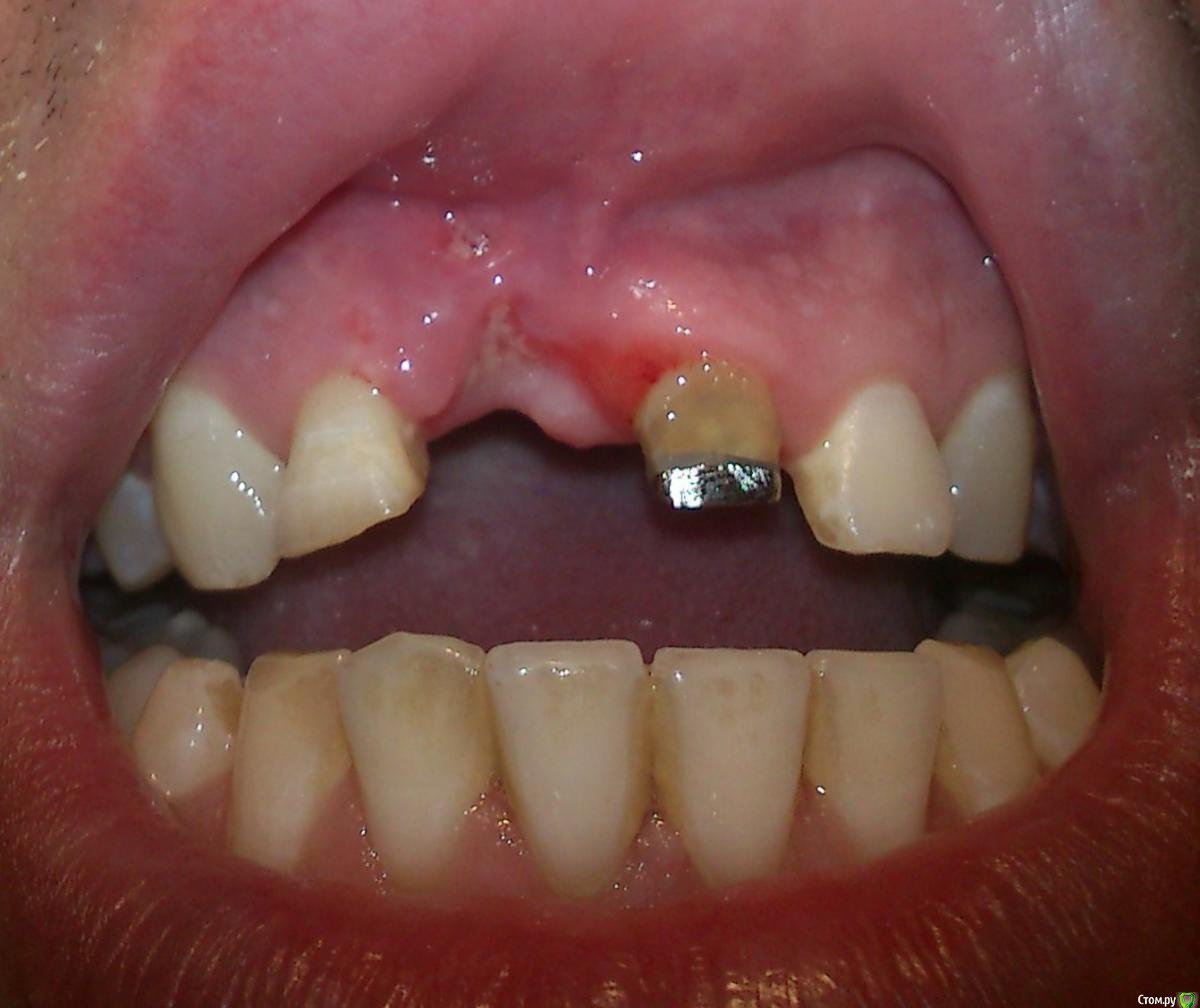

Здравствуйте, необходим свежий взгляд на мою проблему. С раннего детства в возрасте 7-8 лет получил травму, сломав два  верхних передних зуба (11, 21). У них были удалены нервы и запломбированы каналы, в возрасте 17-18 лет надеты постоянные, спаянные коронки. В возрасте 25 лет из-за полученной травмы (неудачного падения) был сломан корень 21 зуба, что привело к его удалению. На второй зуб (11) была установлена культевая вкладка и одета коронка. Через год после удаления решился на имплантацию утраченного зуба. Лечащий врач посоветовал нарастить кость для более правильной и надежной  установки импланта и возможности  дальнейшего протезирования с эстетической точки. Провели костную пластику, установлена была мембрана коллагеновая и подсыпан костный материал (не свой) под нее. То ли у меня отторжение этого материала произошло, то ли из-за недостаточного объема десны инфицировалась мембрана, так как оперирующий меня врач с трудом наложил операционные швы, ему пришлось натягивать десну за счет соответствующих надрезов ее у соседних зубов. Операция длилась около двух часов. Оказывается, у меня срослась десна с костью, или проросла в кость, из-за свича давнишнего, точно не знаю. После операции (3-4 дня) десна в области подсадки костного материала поменяла цвет и начала истончаться и провисать. Десна не заживала, и в месте подсадки костного материала просто рассосалась. Лечащий врач сказал мне, что все заживет со временем и посоветовал наносить пасту Солкосерил дентальный на поверхность дефекта.

post-41404-0-83350500-1418589149_thumb.jpg